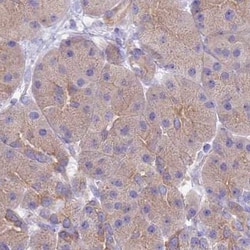

Invitrogen™ STIP1 Polyclonal Antibody

| Immunohistochemistry (Paraffin), Western Blot | |